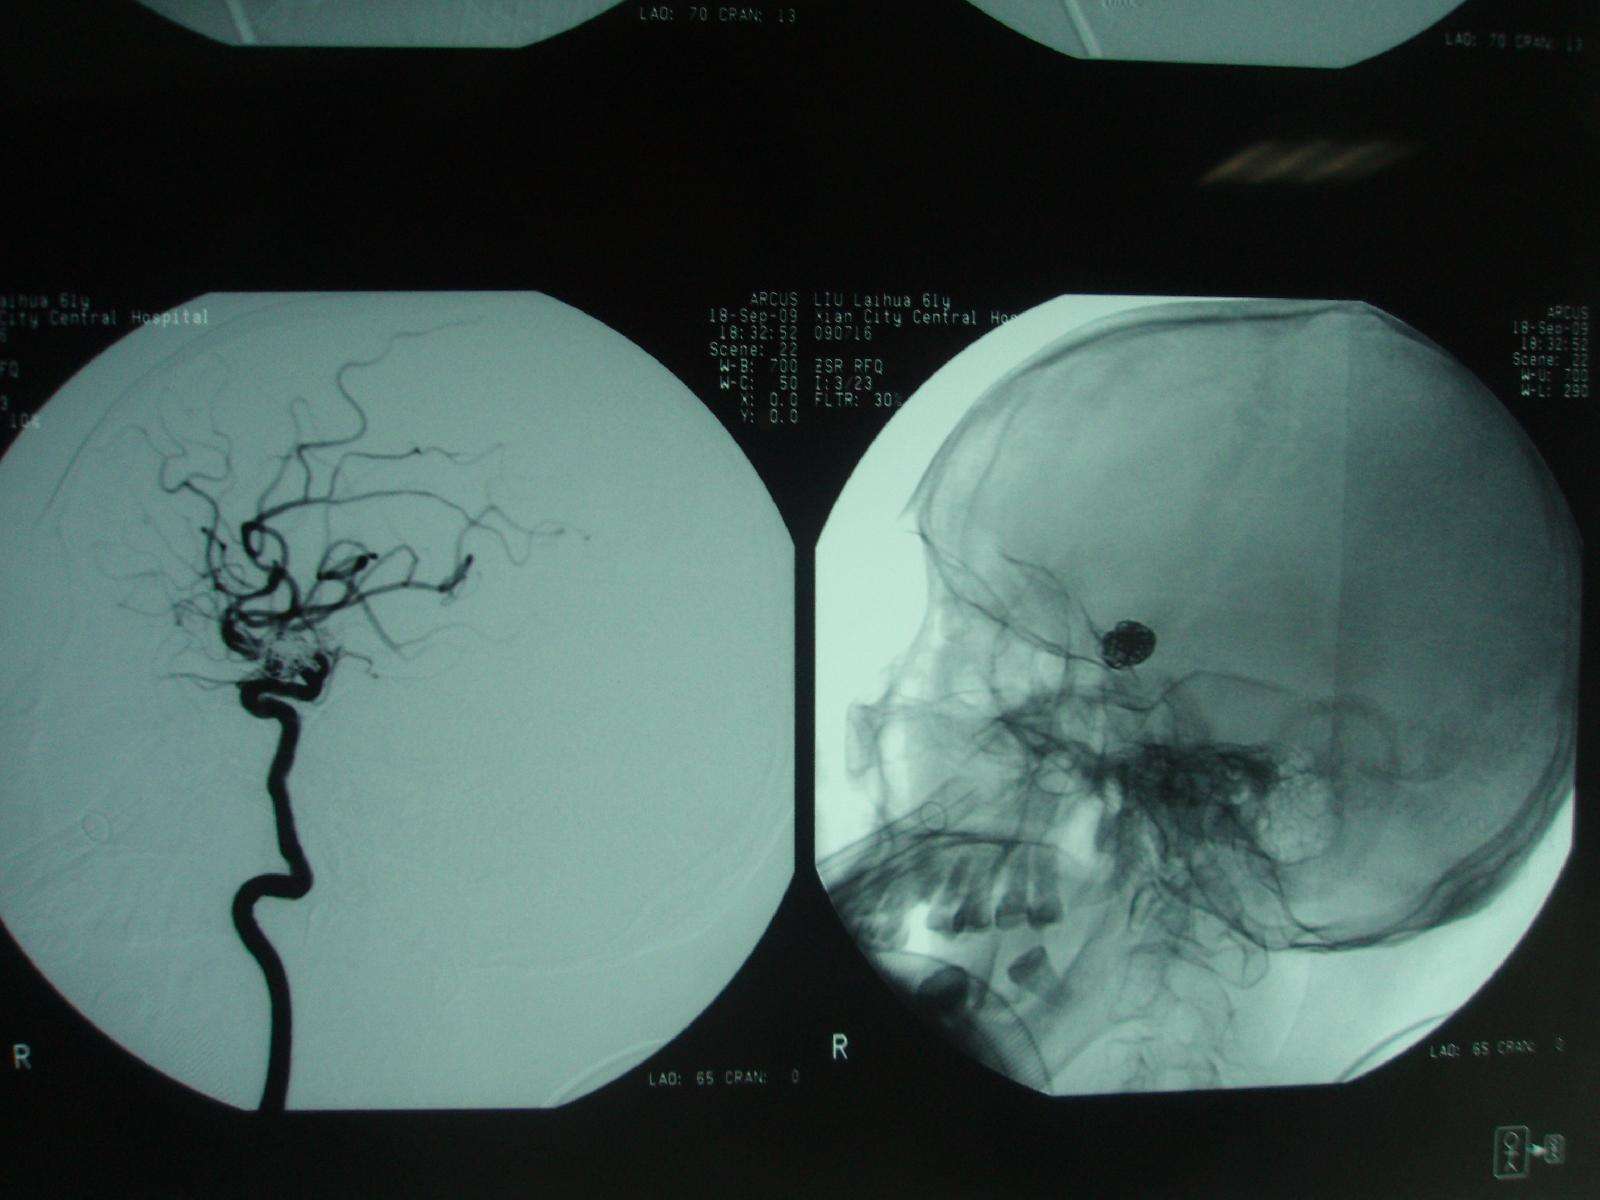

dsa造影显示左侧大脑中动脉受挤压移位,未向肿瘤供血.

急诊脑血管造影提示右侧大脑中动脉m1段闭塞

全脑血管造影术,可见左侧大脑中动脉闭塞